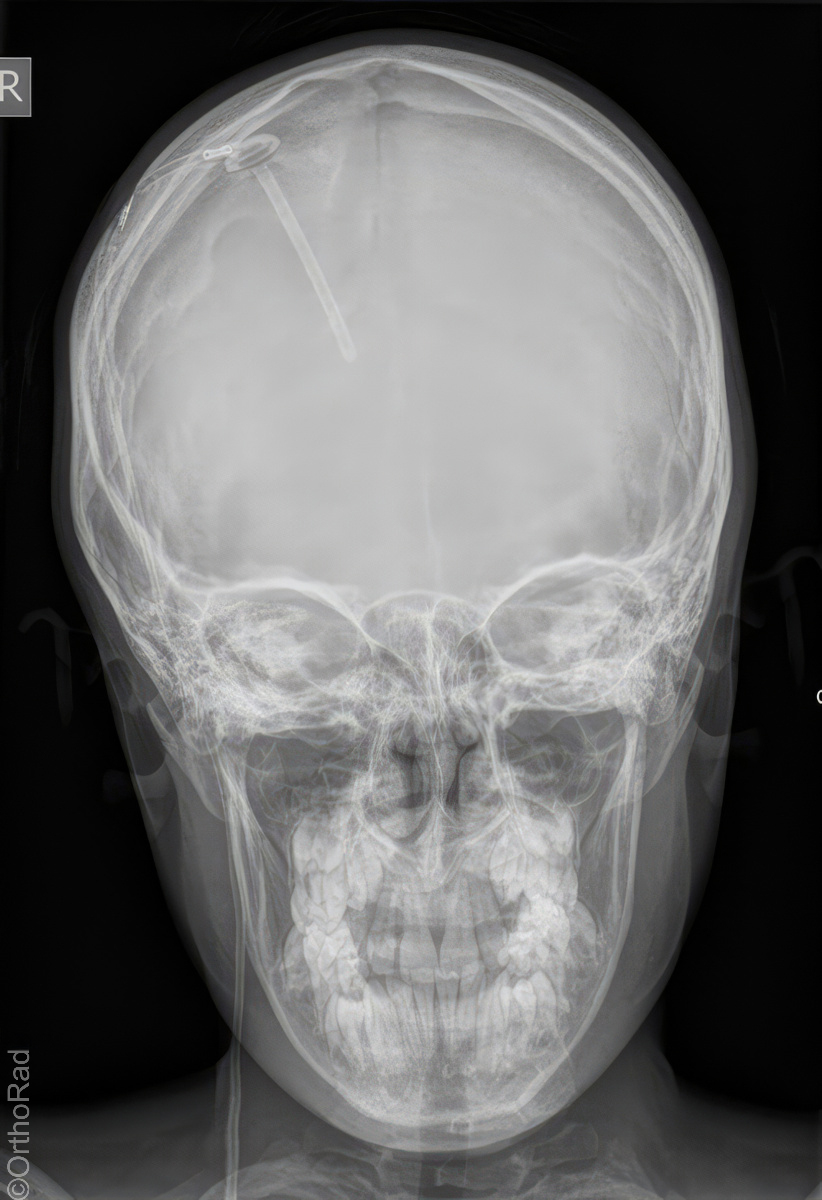

Schädel a.-p.

Indikation

Fremdkörper-Lokalisation vor MRT, Shuntkontrolle

Lagerung

Rückenlage

Schädel liegt exakt gerade

Kinn anziehen bis Deutsche Horizontale senkrecht zur Bildebene

(ggf. 15° Keil unter den Kopf)

Qualitätskriterien

Symmetrische Abbildung beider Schädelhälften, Nasenscheidewand streng in der Mitte. Die Felsenbeine stellen sich im unteren bis mittleren Drittel der Orbita da. Felsbeinspitzen projizieren sich in die Mitte der Orbita oder eher etwas oberhalb davon.